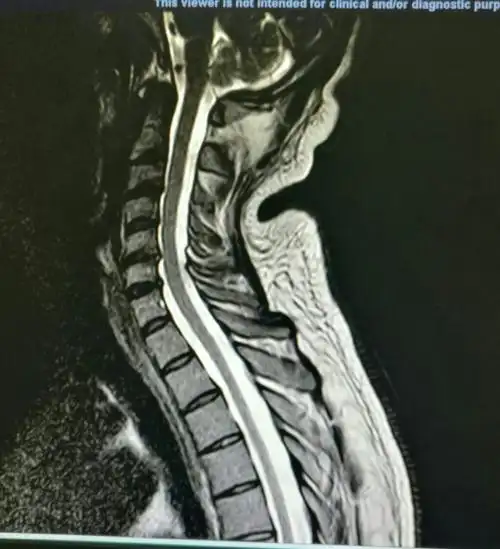

深圳颈椎间盘突出的福音,椎间盘镜微创手术

微创手术治疗颈椎间盘突出继发椎管狭窄 - 好大夫在线

颈椎病 腰椎间盘突出

颈椎突出

其它 颈椎病的微创治疗例一 c6/7后路孔镜术: 例二 c5/6突出症行

颈椎突出,如果一个姿势久了.肩膀僵硬,脖子也很紧.